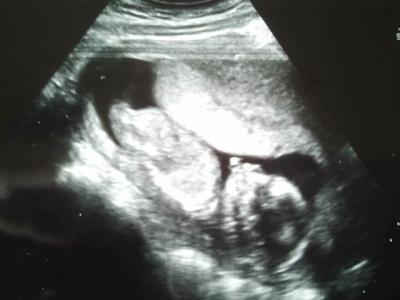

Hallo Leute, ich hatte gestern wieder einen FA-Termin. Dem Baby geht es super ist auf den Tag genau zeitgerecht entwickelt. Und es wird ein Mädchen Das ist natürlich noch nicht hundertprozentig sicher, aber es sah schon ziemlich nach Mädchen aus. Beim nächsten Termin kann man das Geschlecht dann sicher sagen. Sie hat sich diesmal sogar bewegt. Total süß ,aber auch schade, dass man das noch nicht spüren kann . Hier noch das Bildchen von der süßen Maus

Bild zu FA-Termin - Forum für Mai - Mamis